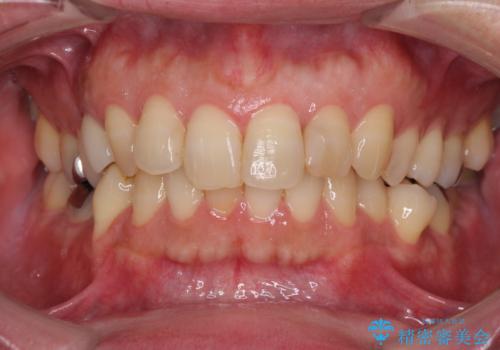

- 外に飛び出した側方の歯と、前歯のデコボコを気にして来院された患者様です。

IPR(歯と歯の間を削る)によってデコボコが解消するように設計し、インビザラインにより治療を行うこととしました。

治療途中で1年半以上通院されない時期があったため、後戻りが生じたことで治療期間が長くなってしまいました。

親知らずを抜去したことで、下顎のデコボコがきれいに解消されました。